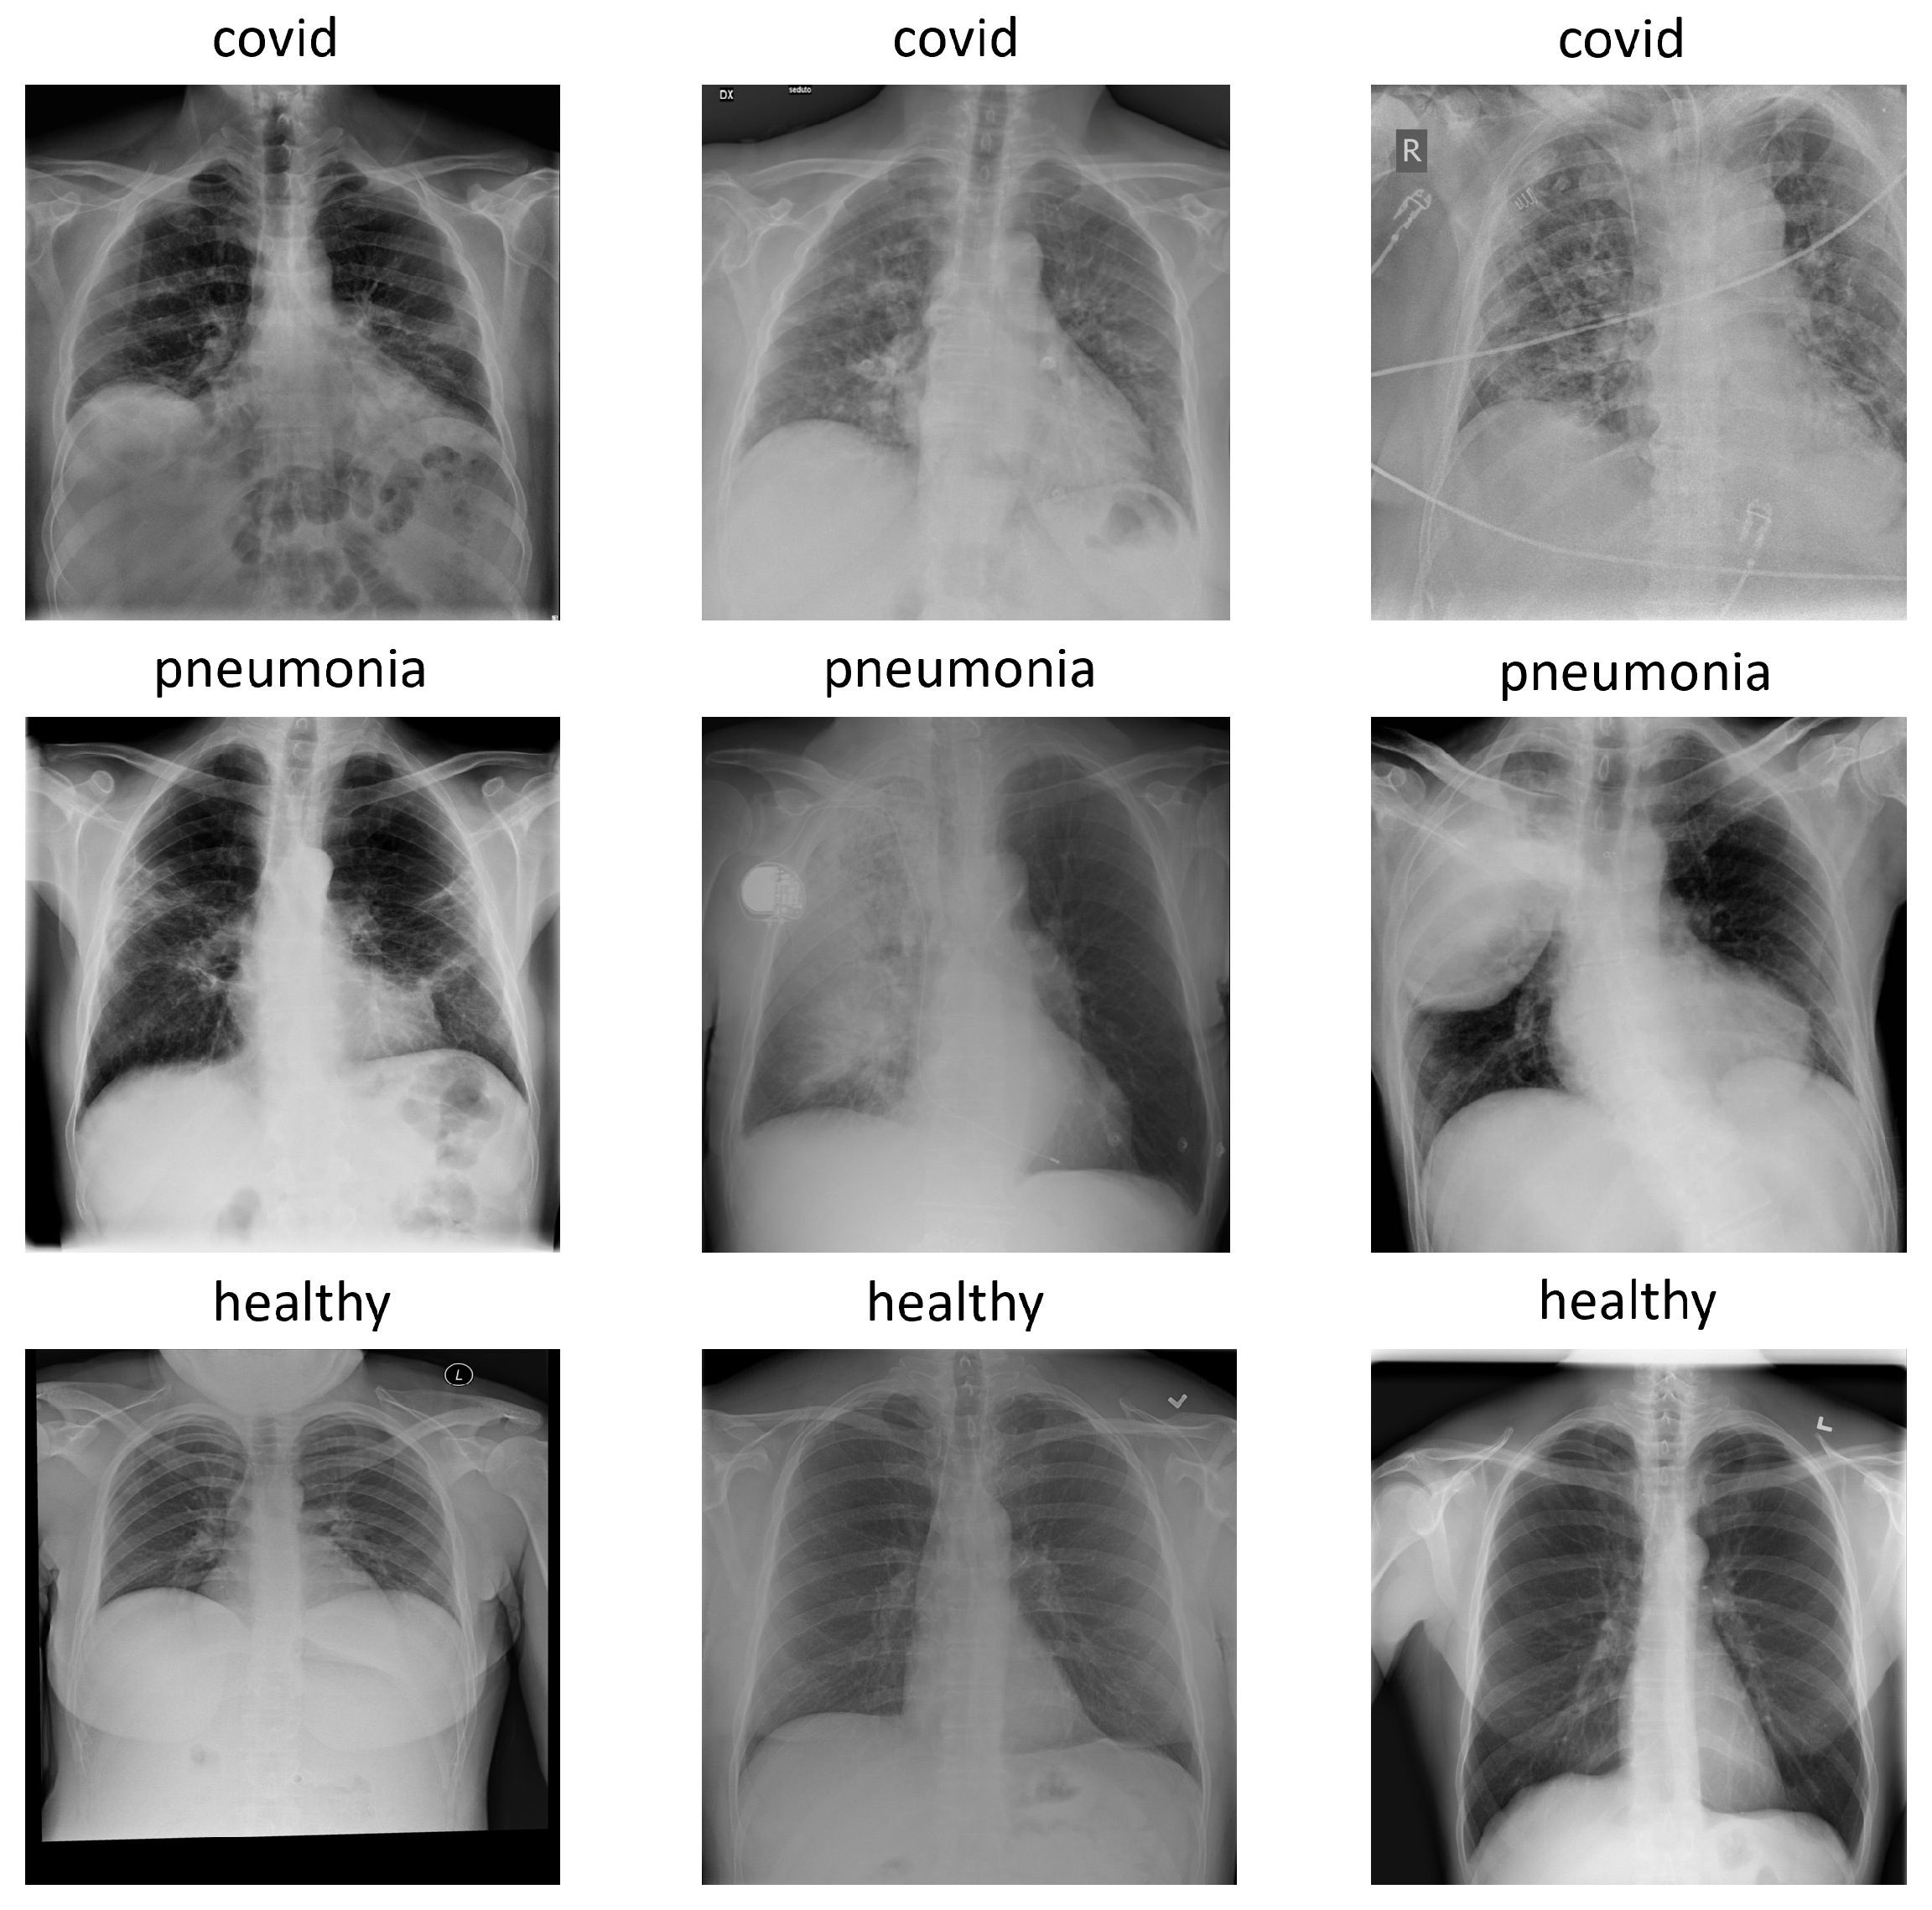

The version used for the experiments was COVIDx7A, which contains 16,690 images with three classes: pneumonia, healthy, and covid. Each image has a 1024 × 1024 size and, for simplicity, is represented in the RGB format with replicated channels. Figure 1 shows an example of each class in the COVIDx dataset.

Figure 1.

Examples of each class in COVIDx dataset: covid, pneumonia and healthy.